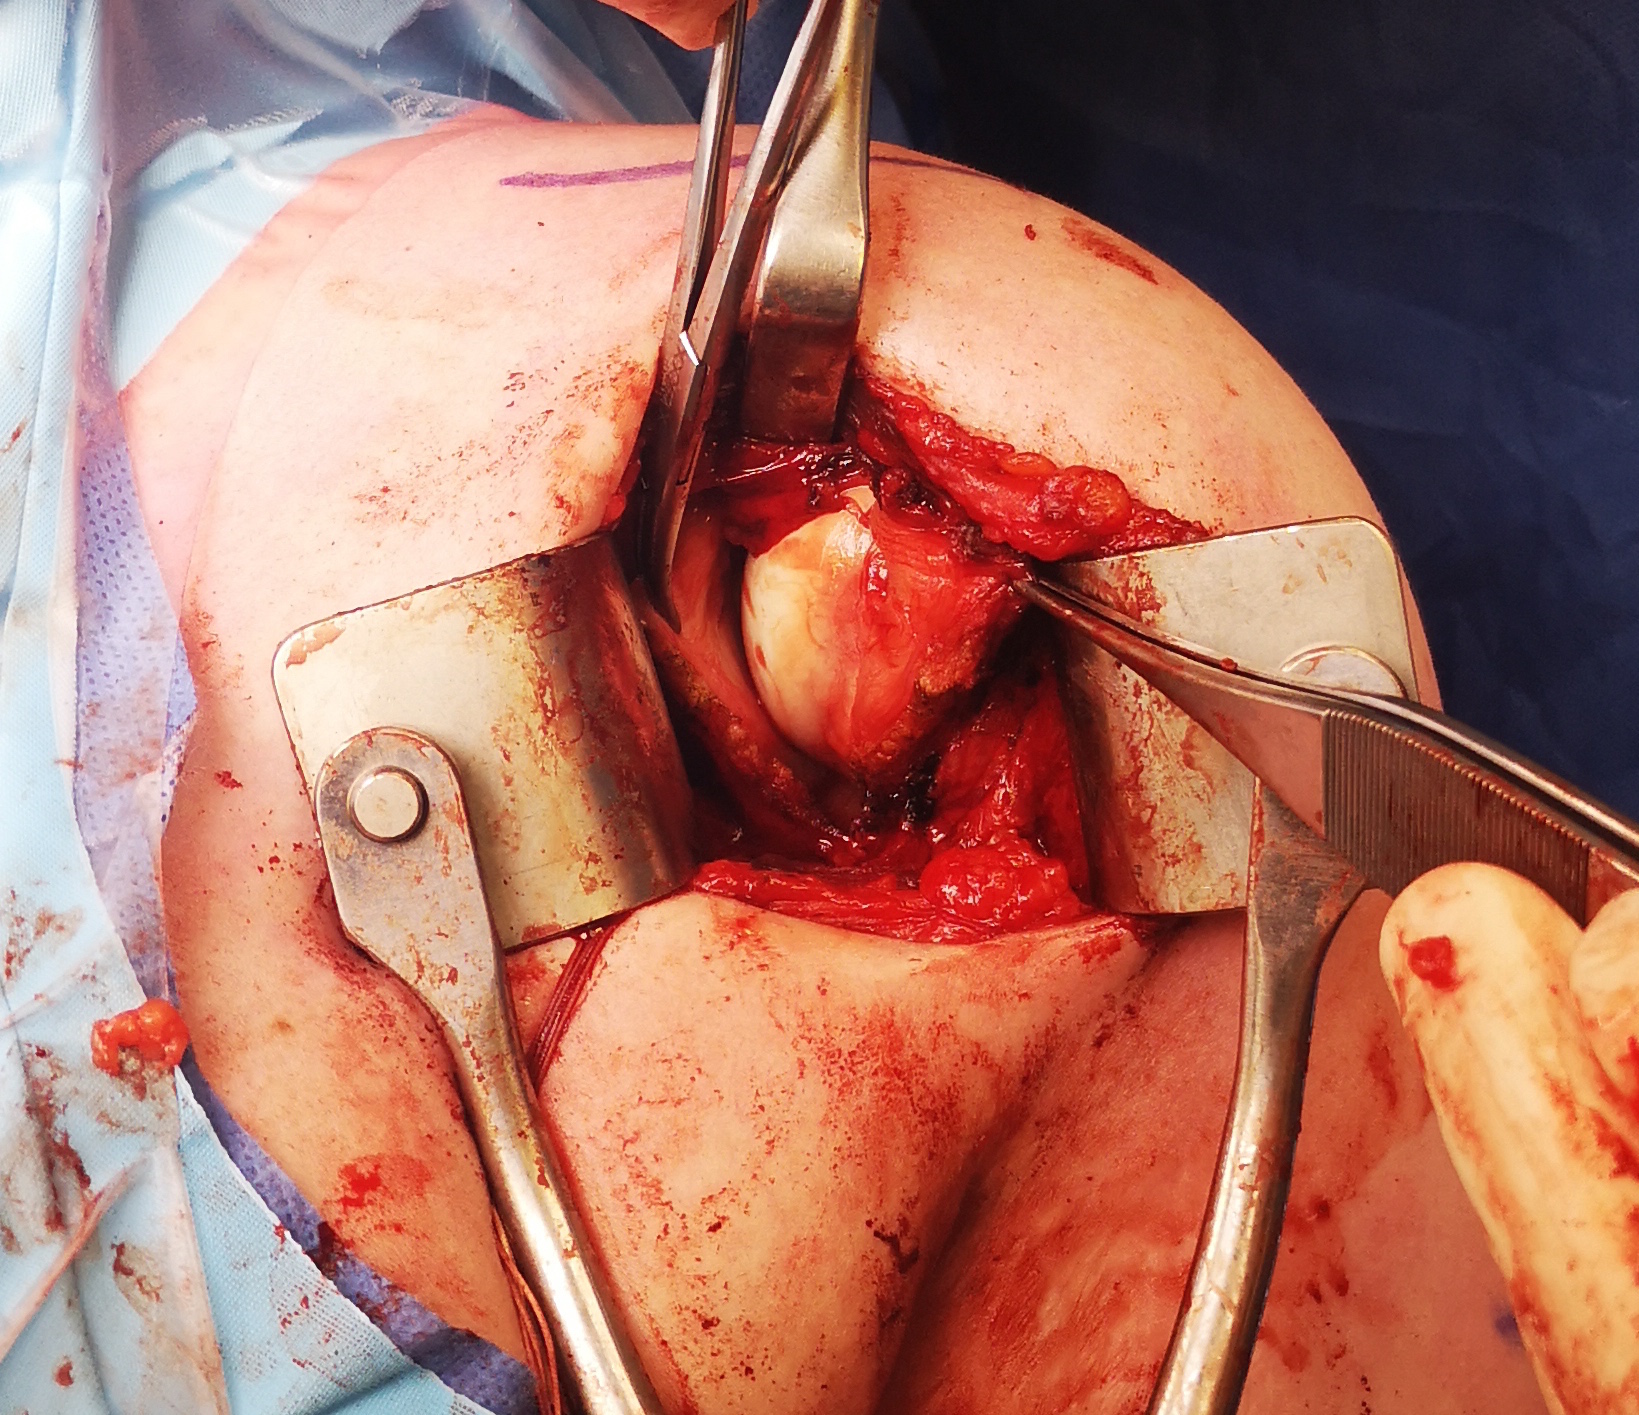

- detach capsule from neck of humerus

- shift capsule superiorly to obliterate the inferior pouch and decrease joint volume

- T shape capsulotomy of capsule

- vertical component on articular margin humeral insertion all the way posterior

- transverse component to midpoint glenoid making superior and inferior flaps

- superior advancement inferior capsular flap

- eliminate inferior pouch and reduce posterior capsular redundancy

- then suture down superior flap